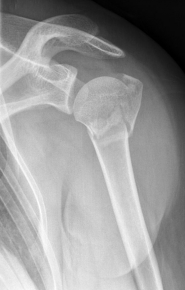

Proximaler Oberarmbruch3Proximaler Oberarmbruch4

Picture: The subcapital humeral fracture shown here in the axis is not broken and only slightly bruised, so that a conservative therapy is possible. The left image shows the follow-up after 3 weeks. The patient has already started physiotherapy. The x-ray shows an increase bone healing.